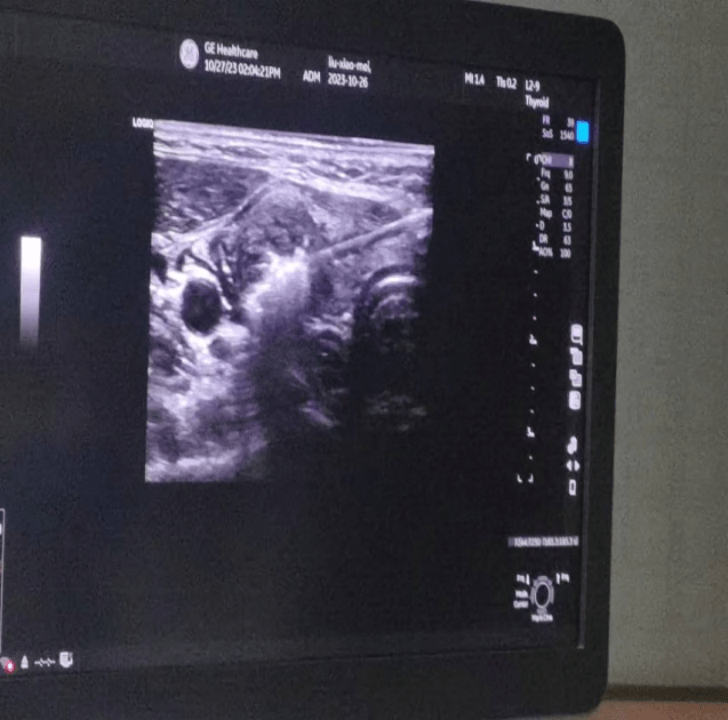

当天,手术在超声介入室进行。在局麻下借助彩超设备对病灶和治疗针具的精确显示和引导,将消融针穿刺到甲状腺病灶内,通过微波产生的高温,引起病灶组织发生局部凝固性坏死,整个手术过程耗时不到30分钟,术后超声造影进一步证实甲状腺结节血供消失,瘤体完全灭活。

△手术前和手术中超声影像对比。